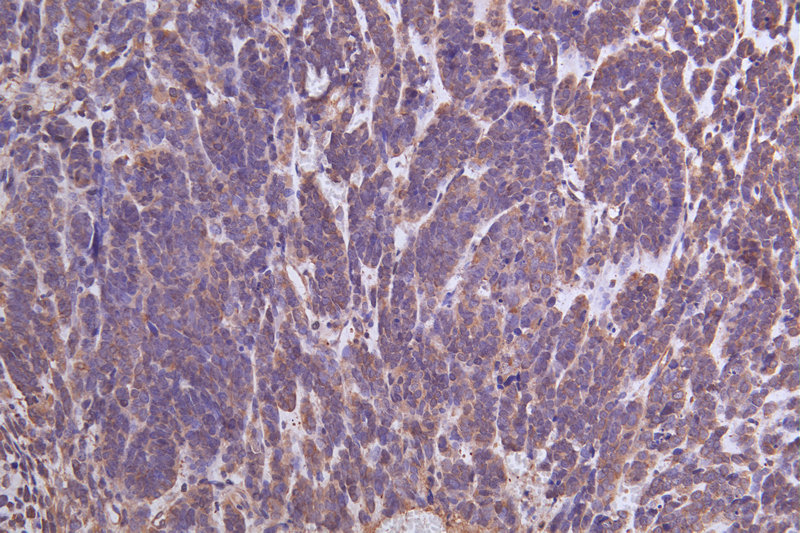

Immunohistochemistry of paraffin-embedded human lung cancer using CSB-PA026288LA01HU at dilution of 1:100